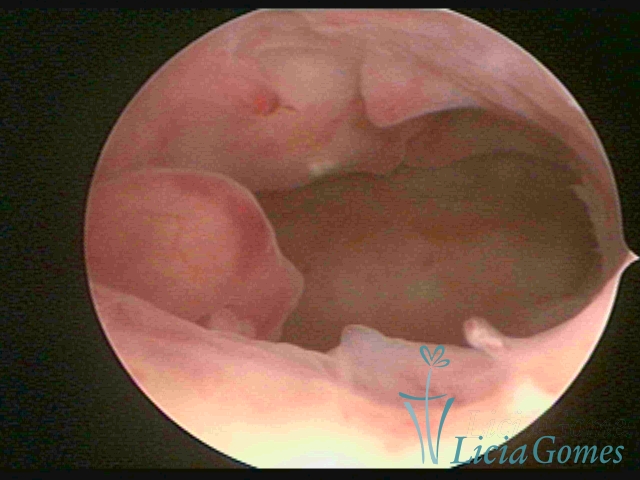

A hipertrofia polipoide é visualizada quando o crescimento endometrial é mais pronunciado, e como o espaço da cavidade uterina é limitado, forma dobras ou sulcos, simulando lesões pseudo polipoides ou polipoides.

A Hiperplasia Complexa tem um aspecto pseudo polipoide, lembrando tecido cerebroide ou com reação deciduoide. A vascularização superficial é mais evidente e com vasos em formatos de saca-rolha ou espirais.